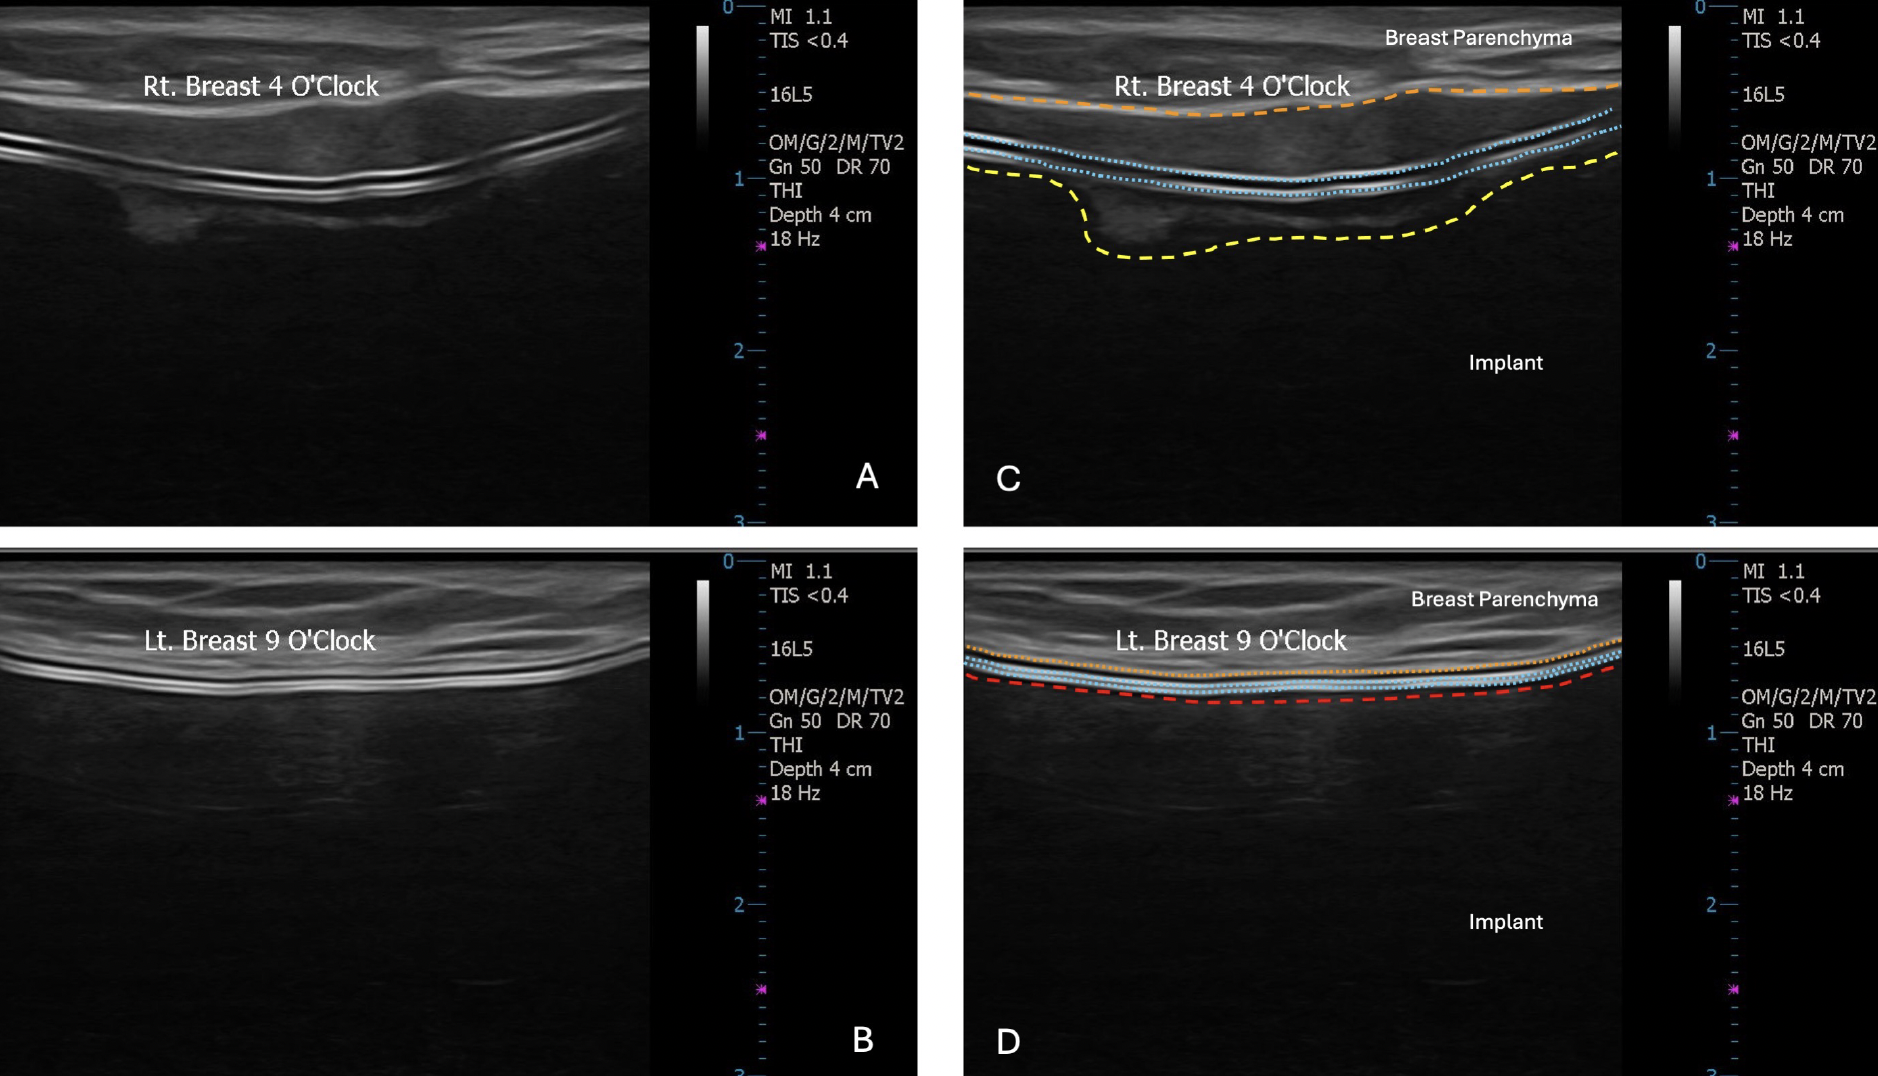

Images A and C on the top show a ruptured implant; images B and D on the bottom show an intact implant. (Glener AD, Sergesketter AR, Adams WP Jr. Outcomes of In-Office, High Resolution Ultrasound Silicone Breast Implant Surveillance by Plastic Surgeons. Aesthet Surg J. 2024 Dec 12;45(1):48-55. doi: 10.1093/asj/sjae165. PMID: 39054844.)